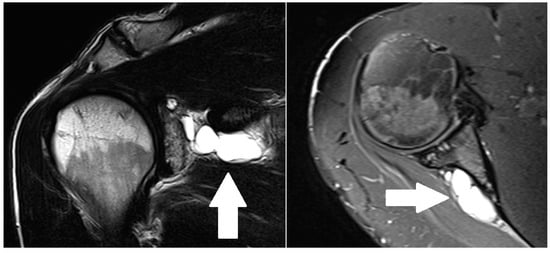

2.4. Radiological Evaluation